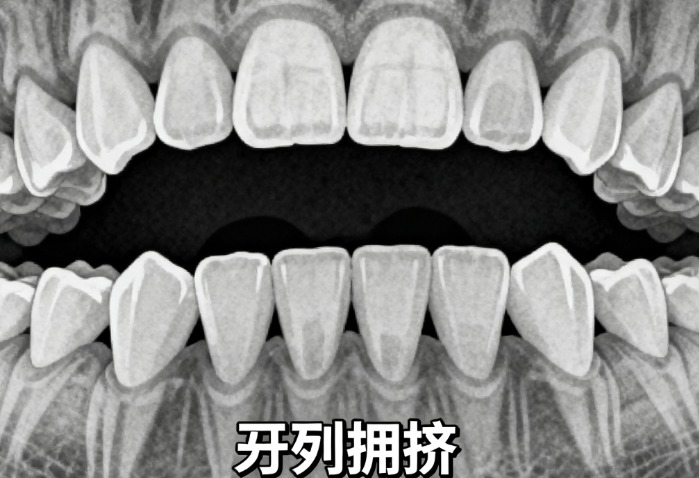

澳洲进口MRC儿童硅胶牙套是专为3-15岁孩子设计的温和矫正方案,用软硅胶引导口腔肌肉调整,不伤牙也不影响吃饭。特别适合乳牙期孩子,能改善地包天、牙弓窄等问题,价格比传统矫正低